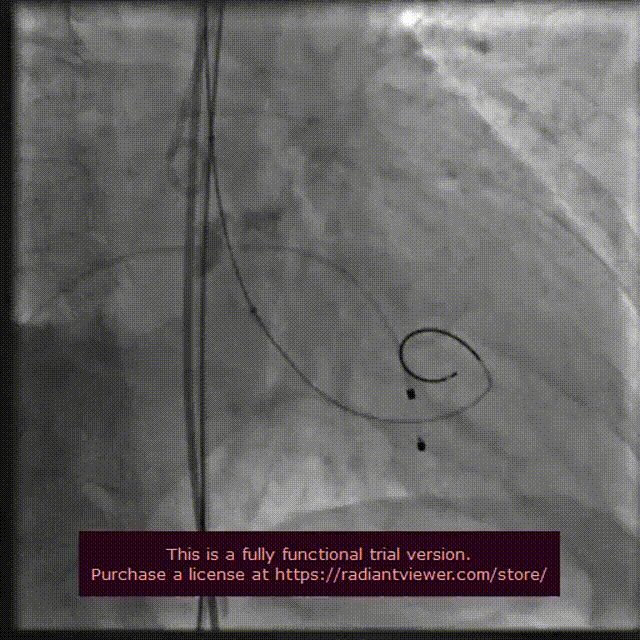

主动脉根部造影

18 mm球囊预扩